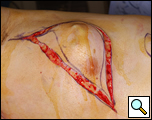

Eleven months later, he presented with a several month history of a painful fixed, firm mass over the pectoral area of the left chest and a smaller mass inferior to this (Figure 1). CT scan demonstrated a new 2 cm nodule in the left upper lobe associated with an anterior chest wall mass six centimeters in size in addition to bilateral new pulmonary nodules (Figure 2). The mass was tethered to the skin and in danger of eroding through it. The patient underwent en-bloc resection of the chest wall and adjacent lung (Figures 3a-c). The resulting defect (Figure 4a) was reconstructed with 2 mm Gore-Tex patch (Figure 4b) and pectoralis major muscle flap (Figure 4c) with primary skin closure (Figure 4d). The pathology revealed metastatic chordoma (Figures 5a-d). The patient recovered well, leaving the hospital on the sixth postoperative day.